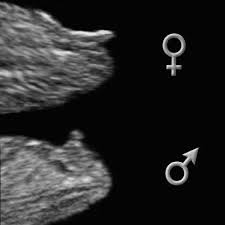

Typically anywhere past 16 weeks is when you can tell. Getty contributor the nub theory. If it is a boy it is boy. If it is moving upward then it is more likely a boy.

The only way to be completely sure of the sex of a baby is to wait until birth. Ultrasounds can now detect a baby s gender as early as 12 13 weeks gestation. Nope it s too tiny to see on an ultra sound. At 13 weeks pregnant baby gender ultrasound is mostly done to determine proper development of the baby but it can also help you determine whether the baby is male or female.